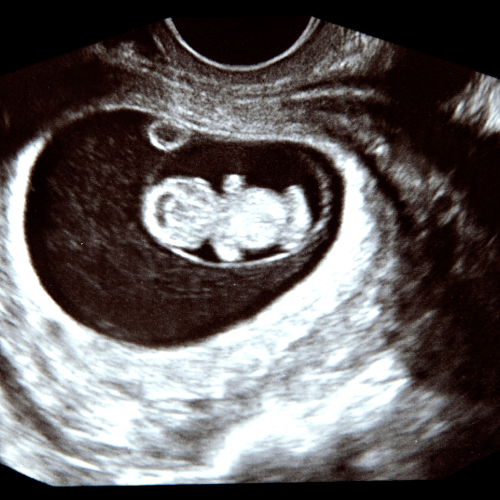

Fetal imaging

In-utero diagnostic

Over the past two decades, Dr. Alam has established an unparalleled reputation as a fetal medicine specialist and radiologist in Kolkata. His expertise encompasses first-trimester screening, fetal echocardiography, non-invasive prenatal testing (NIPT), and diagnostic fetal interventions. Across distinguished clinics—including Care IVF, Fetomat Foundation, Institute of Fetal Medicine—he has managed complex fetal conditions, from abdominal wall defects and fetal growth restriction to interpreting subtle fetal soft markers, always with a patient-centric approach and collaborative care.